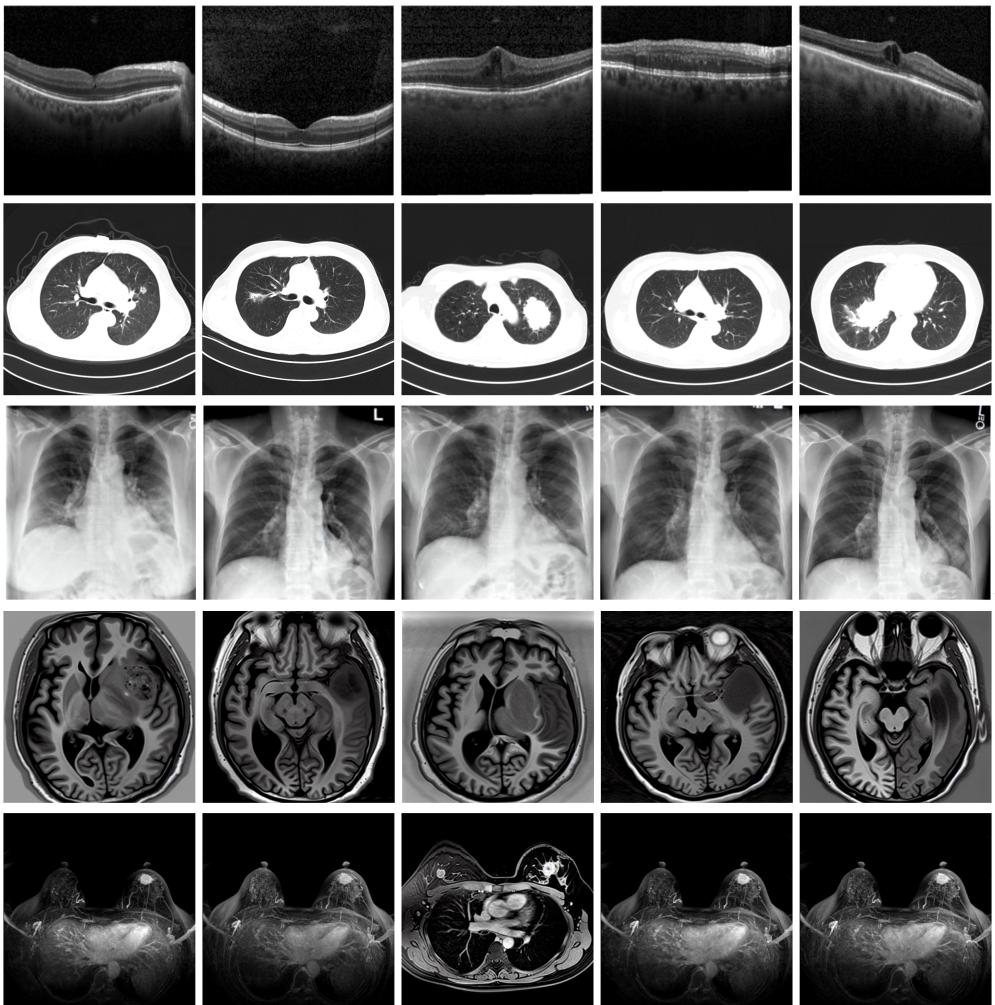

圖為由MINIM生成的高質(zhì)量醫(yī)學合成圖像(受訪者供圖)

“目前公開的醫(yī)學影像數(shù)據(jù)非常有限,我們建立的生成式模型有望解決訓練數(shù)據(jù)不夠的問題?!北本┐髮W未來技術學院助理研究員王勁卓說,研究團隊利用多種器官在CT、X光、磁共振等不同成像方式下的高質(zhì)量影像文本配對數(shù)據(jù)進行訓練,最終生成海量的醫(yī)學合成影像,其在圖像特征、細節(jié)呈現(xiàn)等多方面都與真實醫(yī)學圖像高度一致。

實驗結果顯示,MINIM生成的合成數(shù)據(jù)在醫(yī)生主觀評測指標和多項客觀檢驗標準方面達國際領先水平,在臨床應用中具有重要參考價值。在真實數(shù)據(jù)基礎上,使用20倍合成數(shù)據(jù)在眼科、胸科、腦科和乳腺科的多個醫(yī)學任務準確率平均可提升12%至17%。